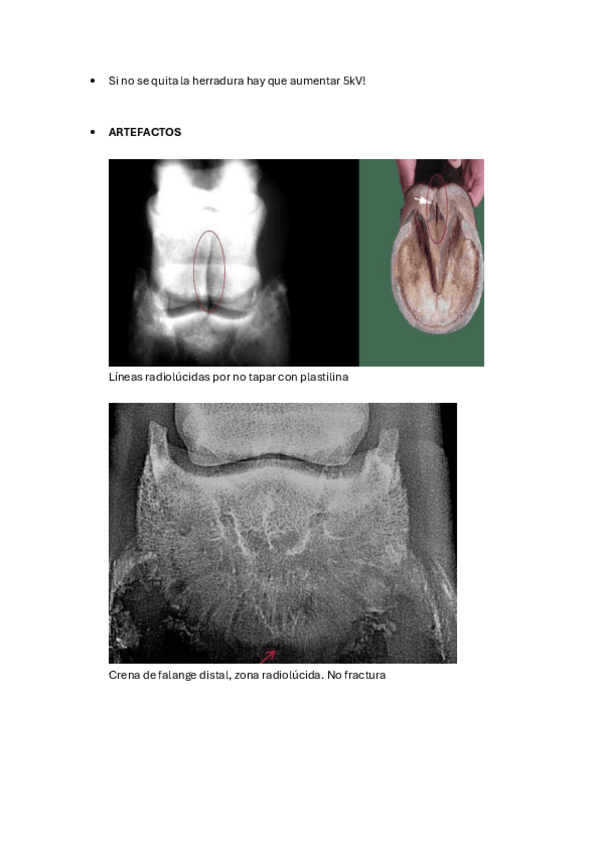

Imágenes de radiografias explicadas

He publicado nuevos apuntes de 3º Diagnóstico Por la Imagen: Imágenes de radiografias explicadas

Rx-equina-1.pdf

Rx-abdomen.pdf

Rx-torax.pdf

Rx-cuello-y-torax.pdf

Rx-miembro-pelviano.pdf

Rx-miembro-anterior.pdf

apuntes